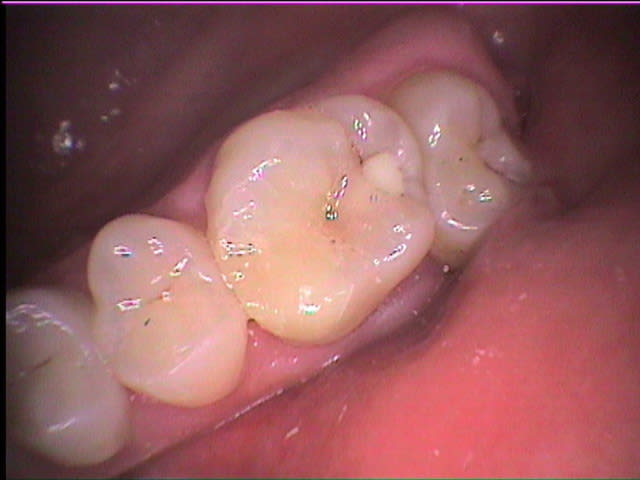

J'aurais aimé savoir ce que les uns les autres vous faites dans ce cas là.

Comparons nos méthodes.

Composite, Amalgame, Inlay, CCM ....

sachant que la limite est juxta gingivale, la gencive n'est pas inflammatoire bien que l'hygiène soit à revoir

patient 25 ans

antagoniste valable

Je précise qu'il n'y avait aucune sensibilité, le patient consultait car son amalgame était parti il y avait une reprise de carie en dessous (première fois que je voyais le patient)

En fait, j'ai fait un composite en technique sandwitch avec un automatrix (je ne me sens pas encore assez doué pour mettre la digue et un automatrix en même temps).

Avantage (je trouve) par rapport à un inlay c'est qu'on est plus économe de tissus d'une part et d'autre part la limite juxta-gingivale (moi j'ai toujours appris qu'un inlay onlay se faisait pour des cavités supra-gingivales, mais je peux me tromper)

Inconvénient: on ne reconstitue pas de façon optimum la cuspide MV (en tout cas je trouve ça difficile), d'où une occlusion imparfaite (n'est-ce pas Isaïe).